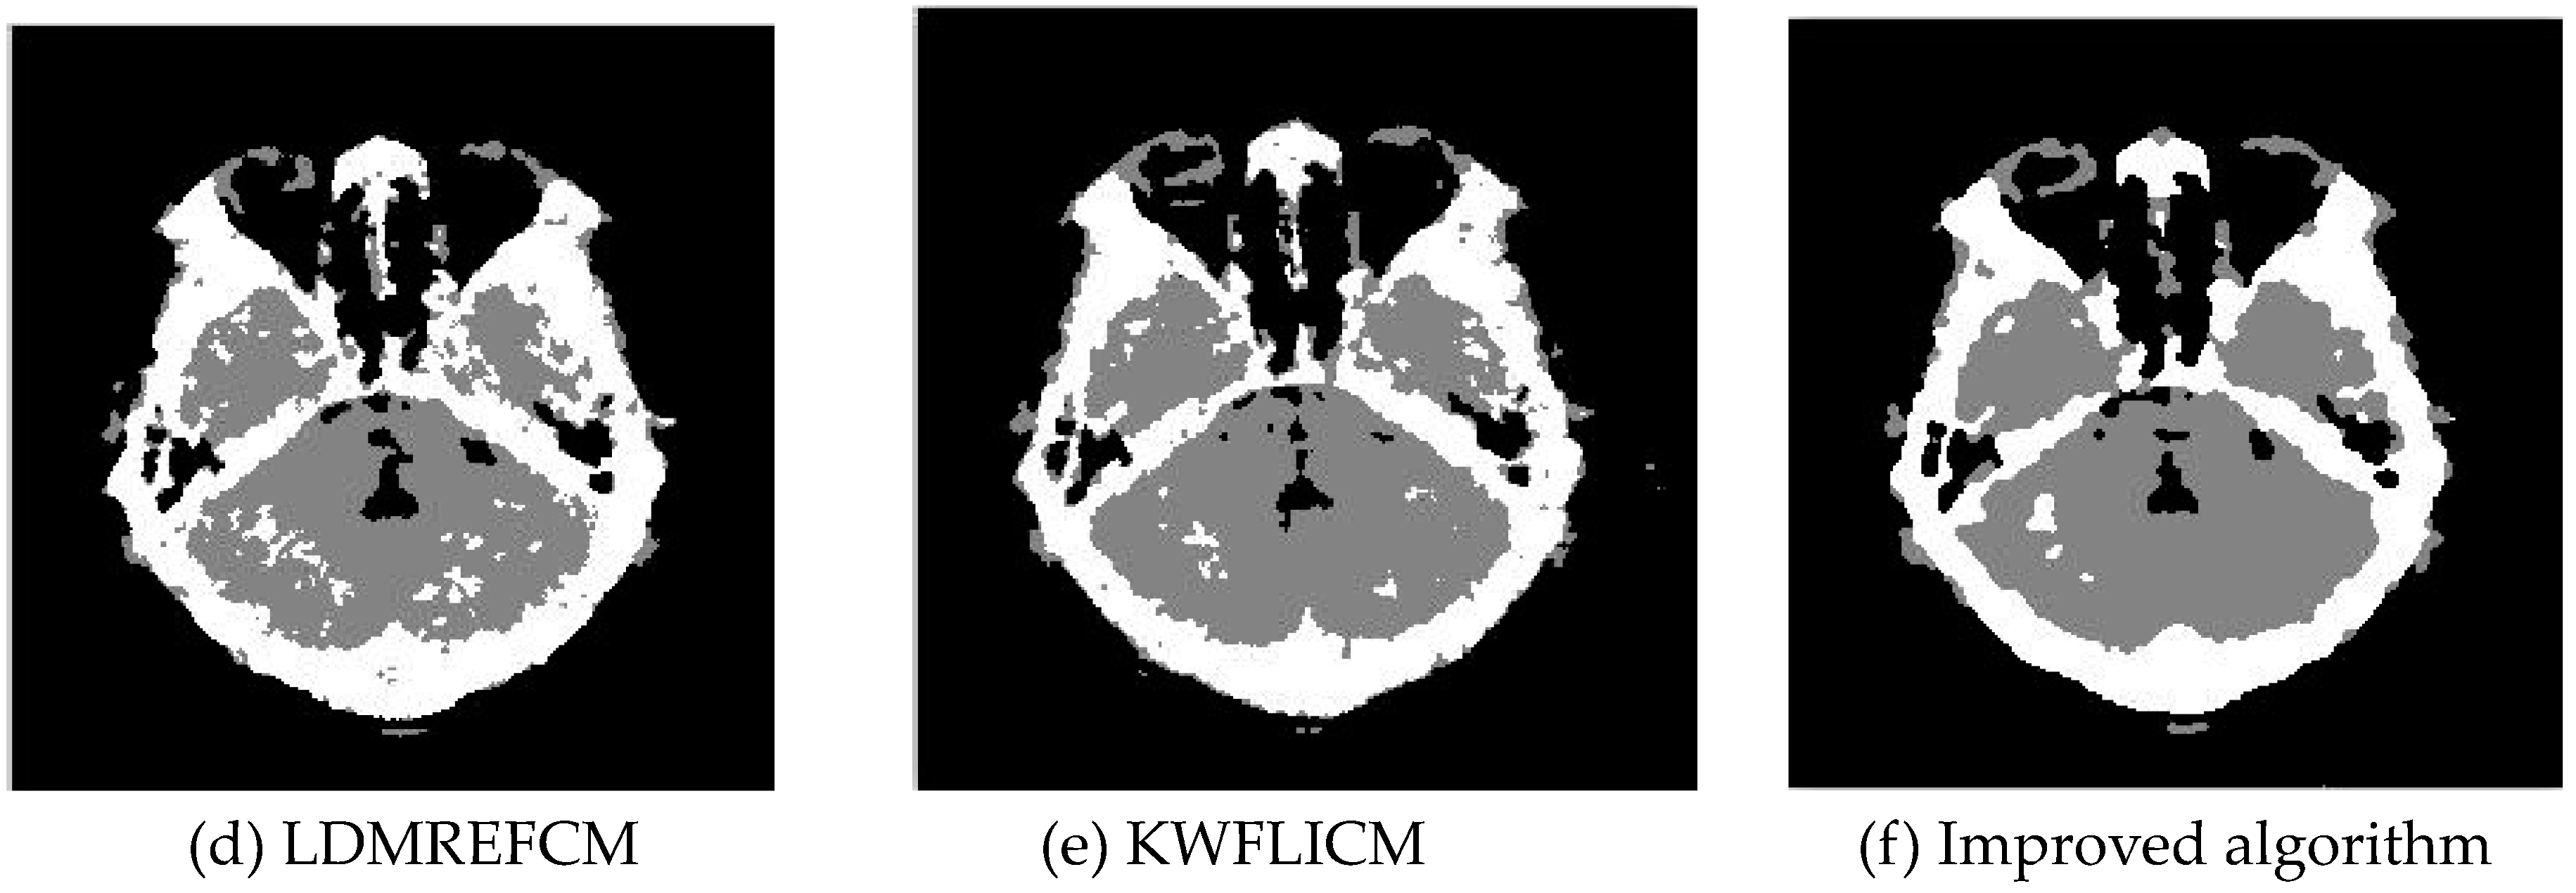

In this experiment, 20% and 40% salt-and-pepper noise were added to two remote sensing images, respectively, while 40% and 30% salt-and-pepper noise were added to brain CT images and images containing four artificial categories, respectively. The experimental results are shown in Figure 6, Figure 7, Figure 8 and Figure 9. The number of clusters was set to 3, 4, 2, and 2. The PSNRs and error rates are shown in Table 4 and Table 5, respectively, and the iterative operation time and number of iterations are shown in Table 6.

3.2.2. Test Result

Comparing the results of image segmentation with the multiplicative noise in Figure 6, Figure 7, Figure 8 and Figure 9, we can see that the FCM_S and FLICM algorithms took neighborhood information into account and suppressed some of the multiplicative noise, but in the case of high noise interference, compared with the improved algorithm, the segmentation results contained a large amount of noise. As seen from the results of the artificial segmentation in Figure 6, Figure 7, Figure 8 and Figure 9, the LDMREFCM algorithm produced the phenomenon of false segmentation. The KWFLICM algorithm and the improved algorithm could remove a large number of noise points. From the test results of the PSNR and the error rate (ERR) of the algorithms in Table 4 and Table 5, along with the iteration times of the algorithms in Table 6, it can be concluded that compared with the PSNR of the FCM_S and FLICM algorithms, the LDMREFCM, KWFLICM, and improved algorithms had a significantly greater noise suppression ability. Table 6 shows that the iteration time of the improved algorithm was the lowest. Although the PSNR of the improved algorithm was 0.7 dB less than that of the KWFLICM algorithm [44,45], the iteration time was 300 s less than that of the KWFLICM algorithm, and the PSNR of the brain CT image segmentation test results in Table 6 was 0.7 dB less than that of the KWFLICM algorithm. However, the iteration time was 45 s less than that of the KWFLICM algorithm. In summary, the proposed algorithm showed a superior performance compared with the FCM_S, FLICM, KWFLICM, and LDMREFCM algorithms, where a large amount of salt-and-pepper noise is suppressed, and the iteration speed of the algorithm was faster.

Figure 8. Salt-and-pepper noise interfering with brain slice images (a) and the segmentation results (bf).

Sensors 20 02391 g008